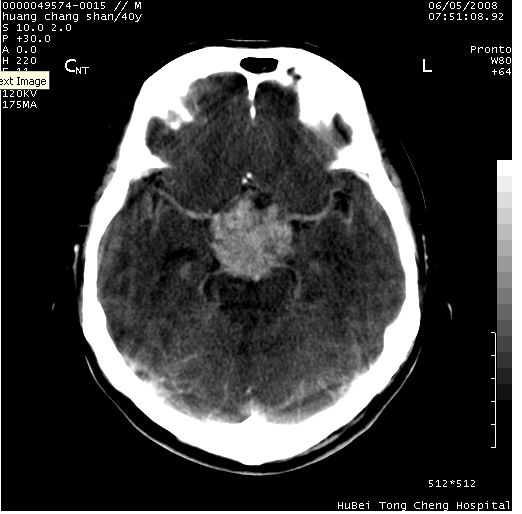

患者 m,40y。头痛,视力模糊,多饮多尿,性欲减退半年余。

行ct平扫+增强,图象如下:

肿瘤强化明显、鞍部骨质结构未见增大、破坏,考虑脑膜瘤可能性大

鞍背无破坏和明显受压,病变明显均匀强化,边界清晰。鞍上区脑膜瘤可能性大,不除外生殖细胞瘤。

平扫病灶呈等密度,增强后强化明显,均匀一致,结合病史首先考虑:垂体瘤。脑膜瘤不支持,因为脑膜瘤平扫多为实性呈均匀高密度影像,内分泌症状多不明显,垂体内分泌素测定正常。

结合临床考虑鞍上生殖细胞瘤可能性大于脑膜瘤(增强未见脑膜围征),建议结合冠状位扫描看病灶起源及垂体窝、鞍底情况。垂体窝内未见明显软组织密度影,垂体窝未见扩大,暂不考虑垂体瘤;病灶较大,未见囊变及钙化,颅咽管瘤不支持。期待结果!

1、头痛,视力模糊,多饮多尿,性欲减退半年余,提示:肿瘤为功能性肿瘤。

2、ct表现:肿瘤呈类圆形,均匀略高密度,无囊变,无钙化。侧脑室有扩大。

3、首先考虑:功能性垂体大腺瘤。

4、鉴别诊断:脑膜瘤,瘤体内点状钙化最具特征性,常位于鞍结节。颅咽管瘤,蛋壳样钙化,常有囊变。动脉瘤,位于鞍旁,强化与动脉一致。有时尚需与发生于鞍区的生殖细胞瘤鉴别,生殖细胞瘤钙化亦较常见。

5、友情提示:下回发现鞍区占位性病变,最好加扫冠状位,了解肿瘤与蝶鞍的关系及蝶鞍骨质的改变。